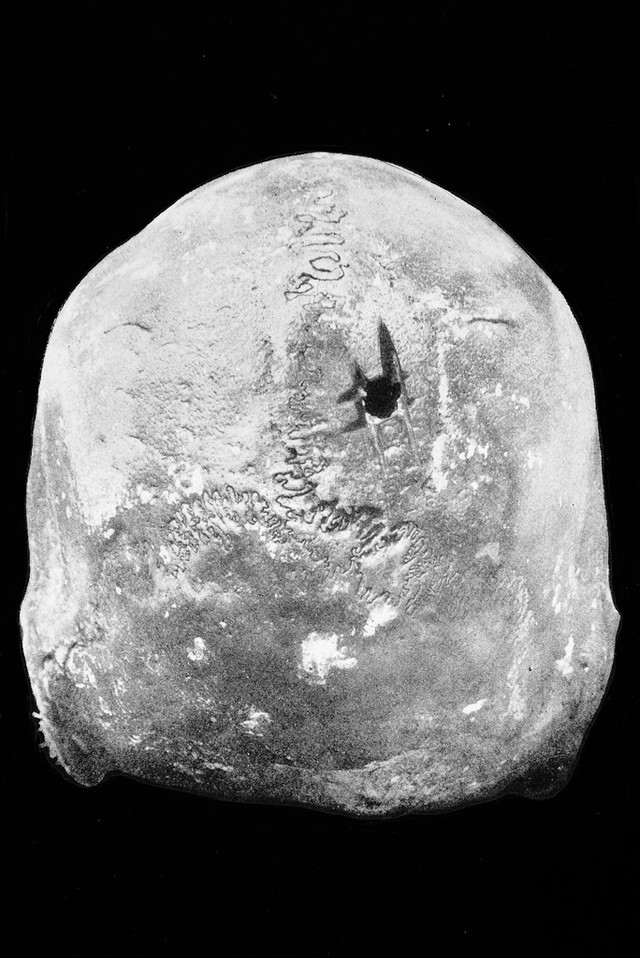

M0006135: Posterior aspect of Cranium 2 from Huarochiri, showing trephinning

Credit: M0006135: Posterior aspect of Cranium 2 from Huarochiri, showing trephinning. Source: Wellcome Collection.